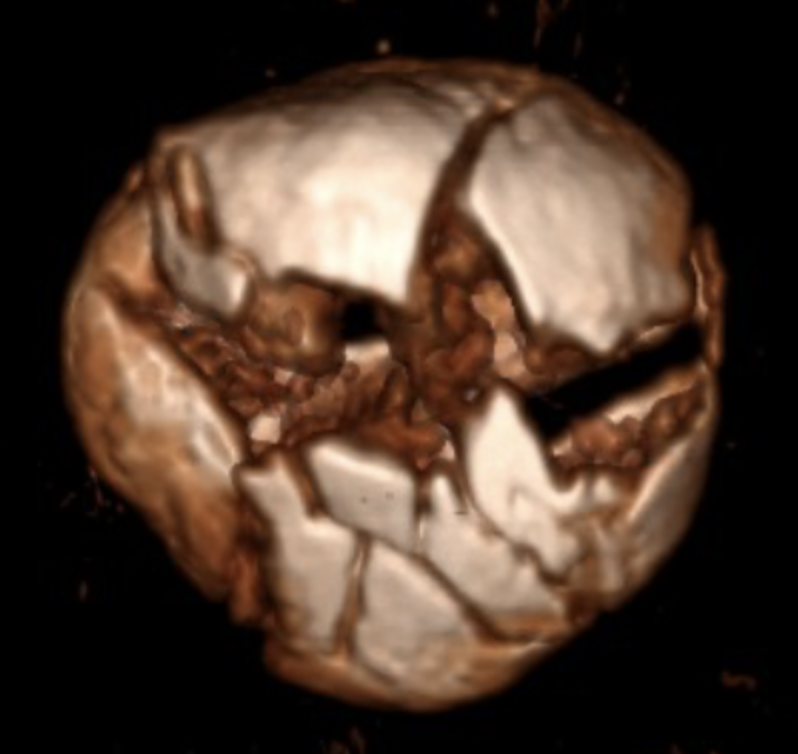

In an incredible three-hour surgery, Dr. Helfet reconstructed my shattered knee cap into no fewer than 20 pieces. Eleven months later, after a flawless recovery, Dr. Helfet and I decided to remove the 10 screws and plate. Once again, he successfully navigated surgery on my genetically fragile bone.